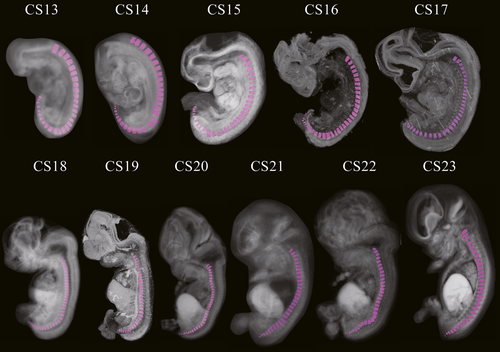

Этапы развития эмбриона человека: 14 недель